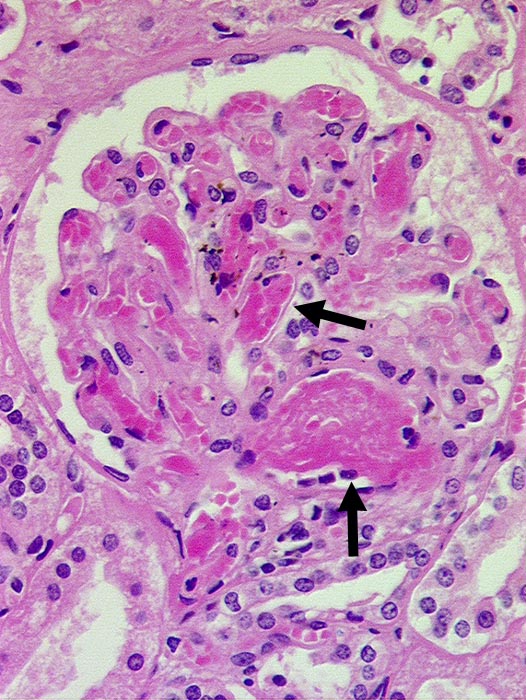

Nierenglomeruli mit DIC

vaskulär / Durchblutungsstörung

Niere

Die glomerulären Gefässe sind angefüllt mit azellulären Fibrinthromben.

Paraneoplastische DIC bei metastasierendem Mammakarzinom